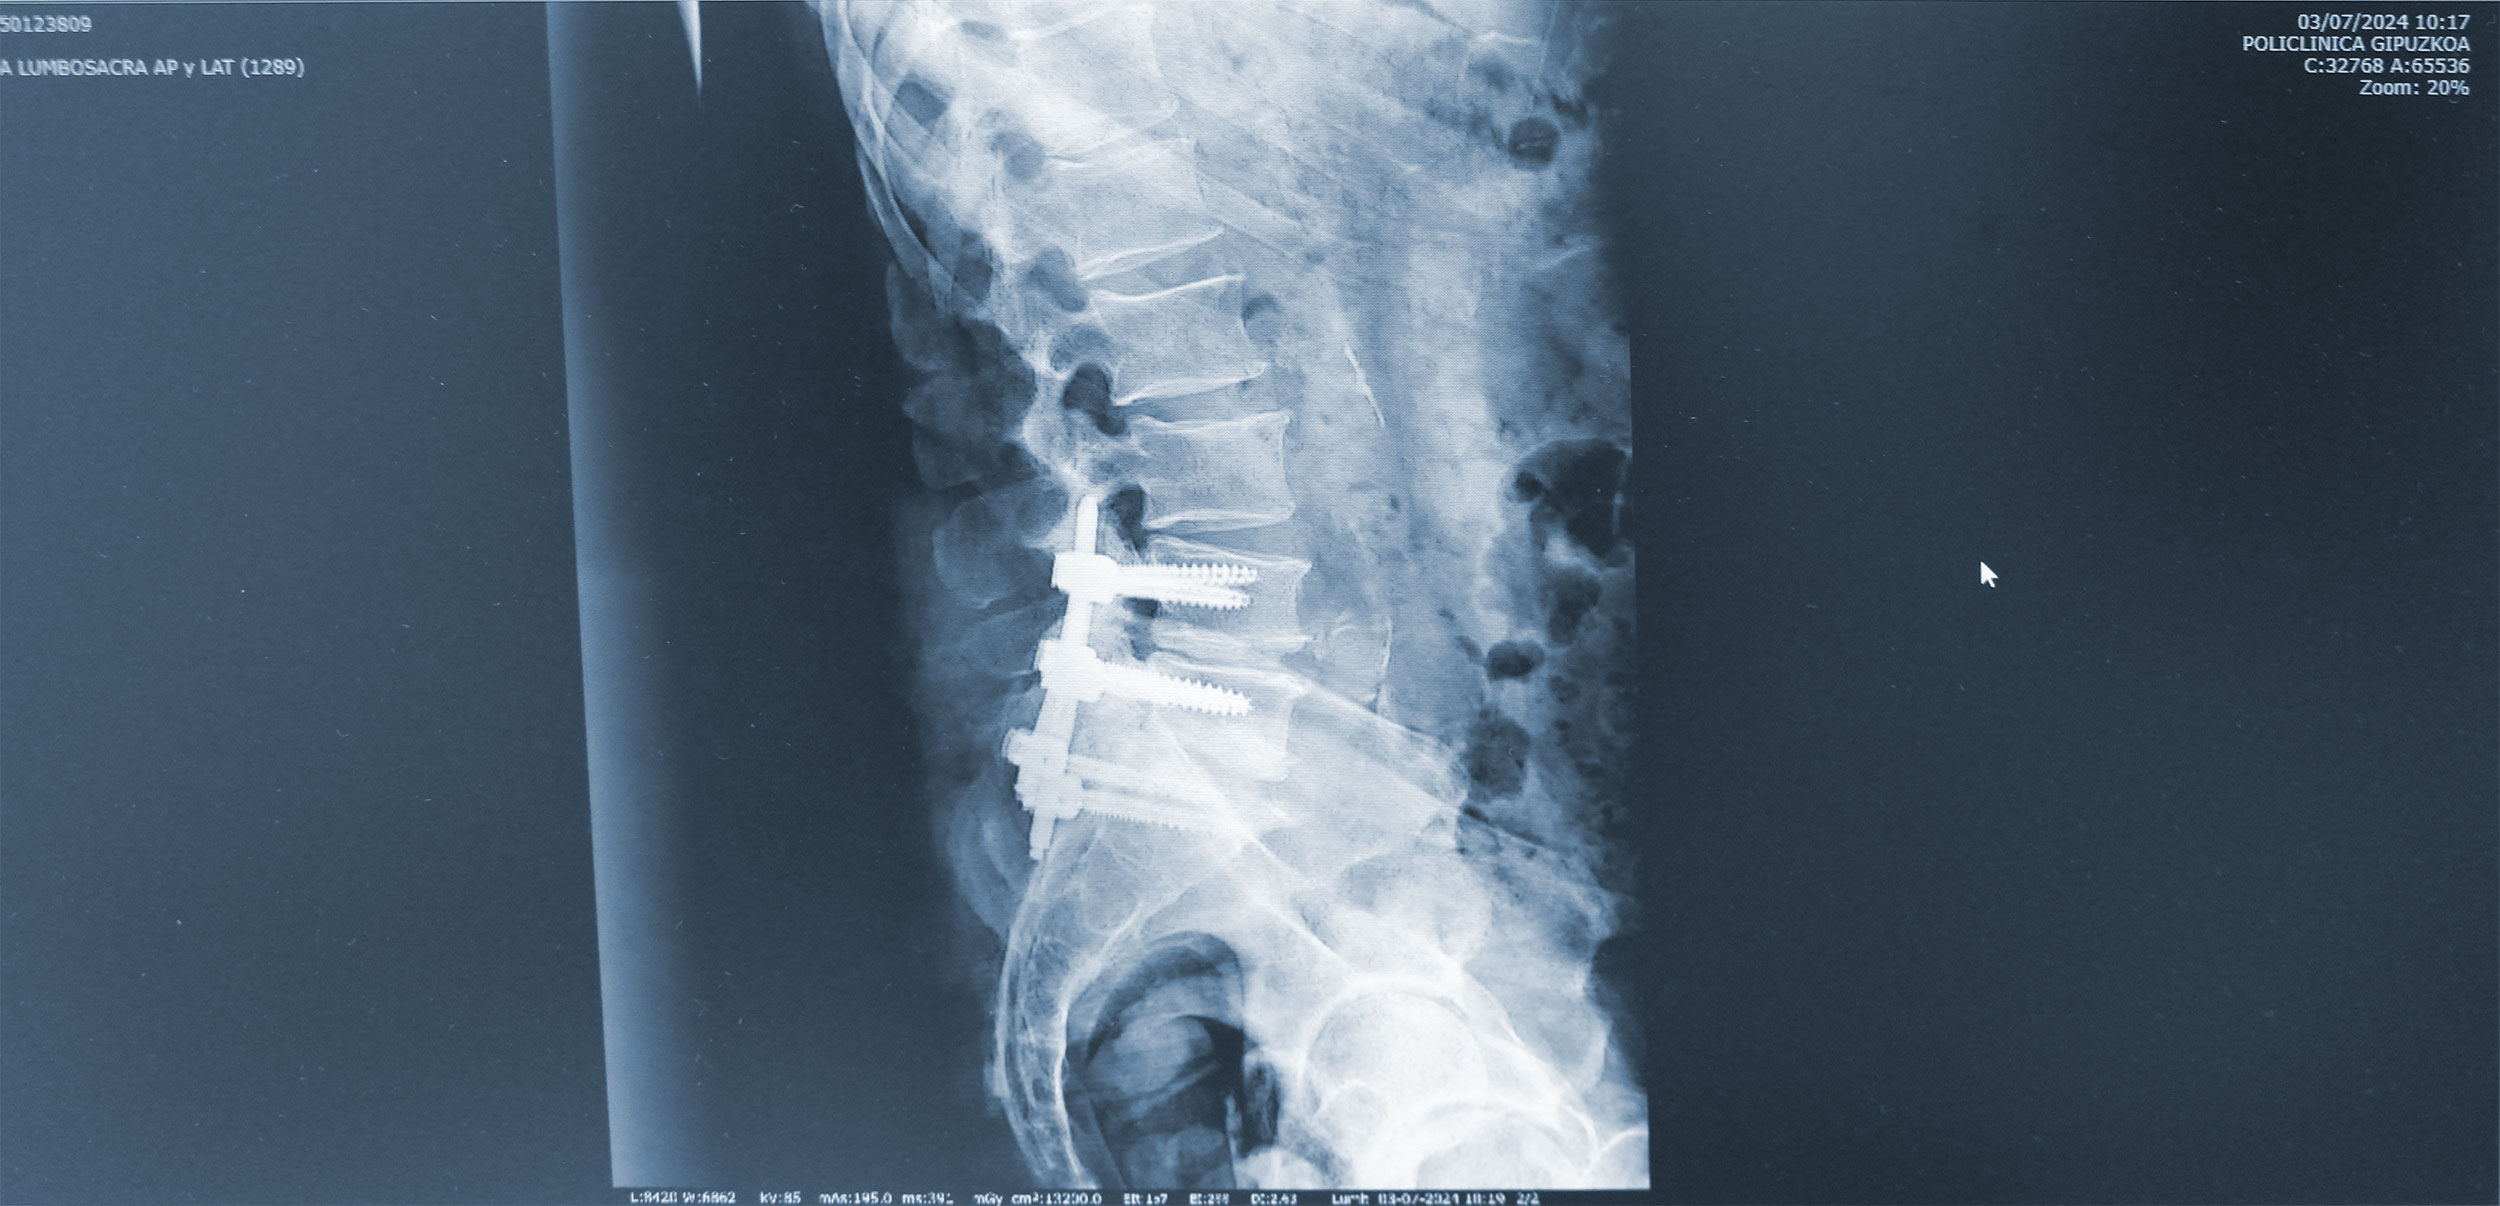

Las revisiones de cirugías previas, la mayoría de ellas mediante cirugía abierta, con persistencia del dolor o incluso con un dolor nuevo que ha aparecido después de la cirugía, son habituales en la consulta, explica el doctor Marqués.

“Cuánto más agresiva es la técnica más secuelas ocasiona”.